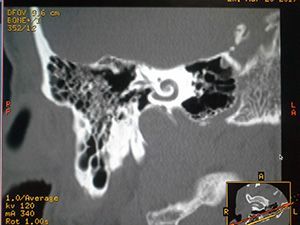

Компьютерная томография височной кости

Компьютерная томография уха — рентгенологический метод диагностического исследования, направленный на получение одновременного изображения мягких и костных тканей данной области. КТ уха показывает структуры ушных отделов, каналы лицевого нерва, ямку луковицы яремной вены, сонную артерию, проч. Данный метод эффективен в том случае, если необходимо определить природу тугоухости. Выполнение КТ уха после травм позволяет вывить плоскость, в которой имеется перелом, и наличие смещений височных костей. Благодаря компьютерной томографии уха можно определить наличие процессов воспалительной природы, а также новообразования уха.